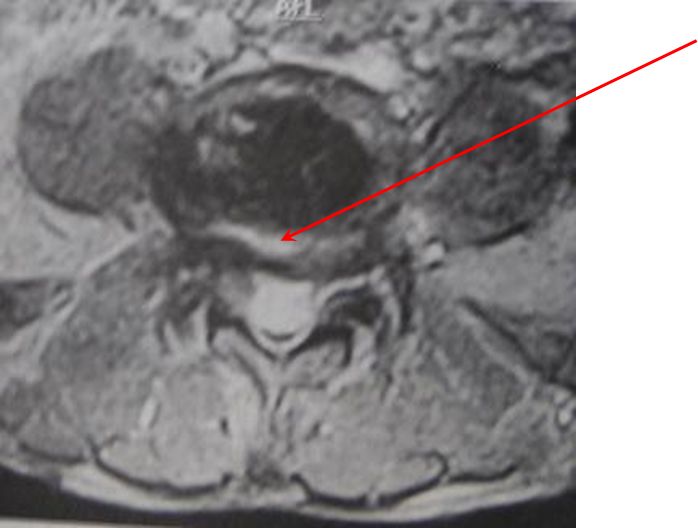

核磁共振检查(MRI)

核磁共振检查(MRI)可观察腰椎神经根受压情况及各椎间盘退变程度,有助于确定减压和融合范围。

椎弓峡部崩裂面粗糙的低信号带

双关节征、双边征和椎间盘夹心征